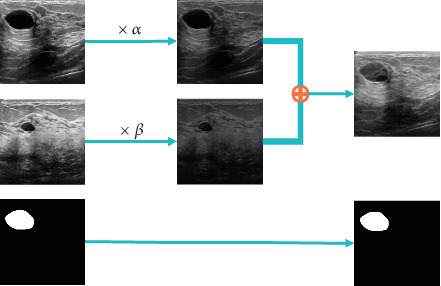

Automated lesion segmentation in ultrasound (US) images based on deep learning (DL) approaches plays a crucial role in disease diagnosis and treatment. However, the successful implementation of these approaches is conditioned by large-scale and diverse annotated datasets whose obtention is tedious and expertise demanding. Although methods like generative adversarial networks (GANs) can help address sample scarcity, they are often associated with complex training processes and high computational demands, which can limit their practicality and feasibility, especially in resource-constrained scenarios. Therefore, this study is aimed at exploring new solutions to address the challenge of limited annotated samples in automated lesion delineation in US images. Specifically, we propose five distinct mixed sample augmentation strategies and assess their effectiveness using four deep segmentation models for the delineation of two lesion types: breast and thyroid lesions. Extensive experimental analyses indicate that the effectiveness of these augmentation strategies is strongly influenced by both the lesion type and the model architecture. When appropriately selected, these strategies result in substantial performance improvements, with the Dice and Jaccard indices increasing by up to 37.95% and 36.32% for breast lesions and 14.59% and 13.01% for thyroid lesions, respectively. These improvements highlight the potential of the proposed strategies as a reliable solution to address data scarcity in automated lesion segmentation tasks. Furthermore, the study emphasizes the critical importance of carefully selecting data augmentation approaches, offering valuable insights into how their strategic application can significantly enhance the performance of DL models.

Abstract Image